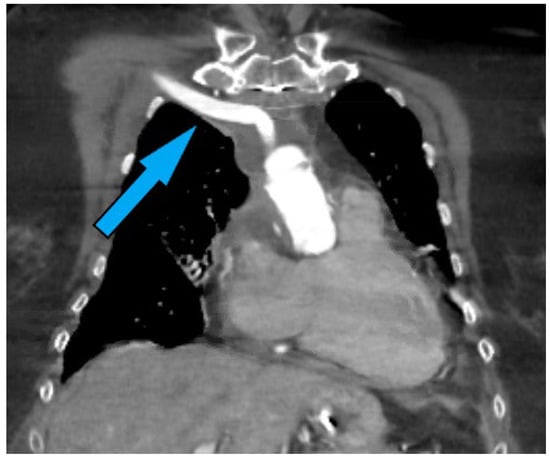

6.2. Preoperative Considerations When Assessing Peripheral Cannulation Options

High-resolution CT scans are invaluable in the preoperative assessment, offering detailed cross-sectional images of the thoracic cavity. These scans can identify the location and extent of aortic disease, the presence of calcifications, and the status of potential cannulation sites. CT angiography provides a detailed view of the aortic anatomy, enabling the surgical team to plan the cannulation strategy effectively. The visualization of a “stump” (Figure 4) in the axilla or other indicators of previous graft placements can significantly influence the choice of cannulation site, highlighting areas where caution is needed due to previous surgical alterations.

While not as detailed as CT scans, chest X-rays can still offer valuable insights into the overall thoracic anatomy, the position of the heart and aorta, and the presence of surgical clips from previous operations. These clips can serve as markers for previous surgical sites, guiding the surgeon in avoiding areas with dense adhesions or compromised vessel integrity.

In the context of redo FET procedures, the challenge in accessing the chest in the presence of extensive adhesions or encountering an extra-anatomical bypass (Figure 5) from a previous intervention necessitates a nuanced approach. Surgeons may opt for peripheral cannulation as a precursor to sternotomy, thereby establishing CPB and ensuring hemodynamic stability before navigating the adhered mediastinum. This strategy not only facilitates safer entry into the chest but also mitigates the risk of inadvertent injury to vital structures [46].